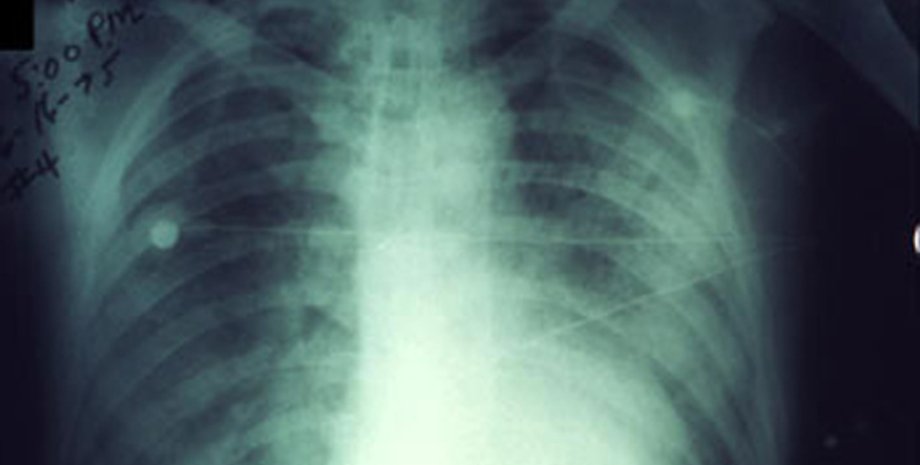

Легочная чума – одна из трех основных форм проявления чумы. Вызывается бактериями Yersinia pestis и поражает органы дыхания. Более опасна, чем бубонная чума, но встречается реже. При отсутствии лечения смертность чрезвычайно высокая, вплоть до 100%.